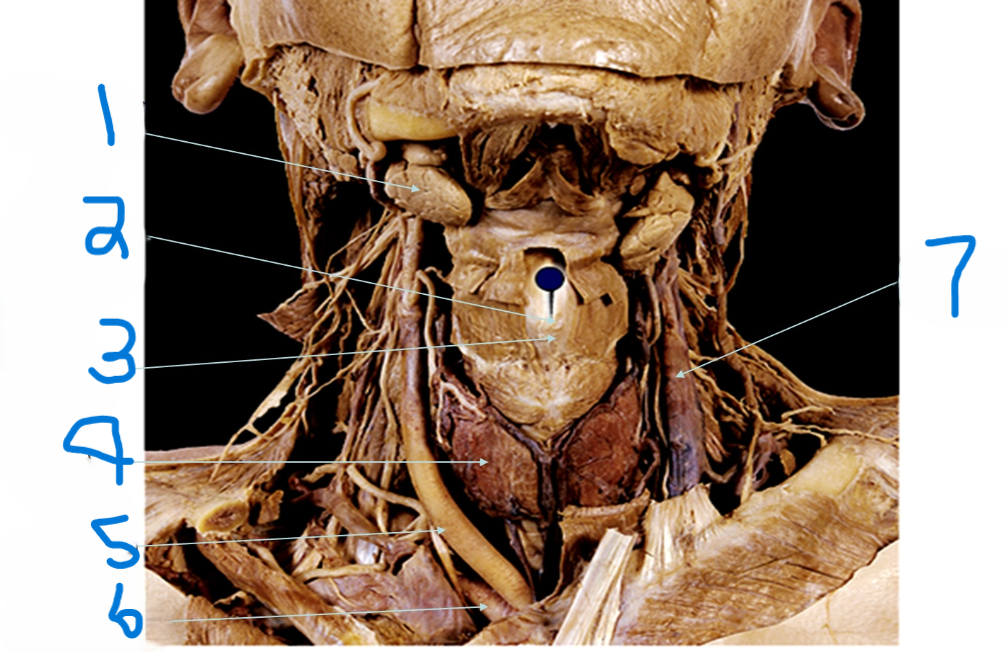

What is depicted by #1

Laryngeal Prominence (adams apple)

What is depicted by #2

Thyroid cartilage

What is depicted by #3

Thyroid gland

What is depicted by #4

Right common carotid artery

What is depicted by #5

Right subclavia artery

What is depicted by #6

Left internal jugular vein

What is depicted by #7